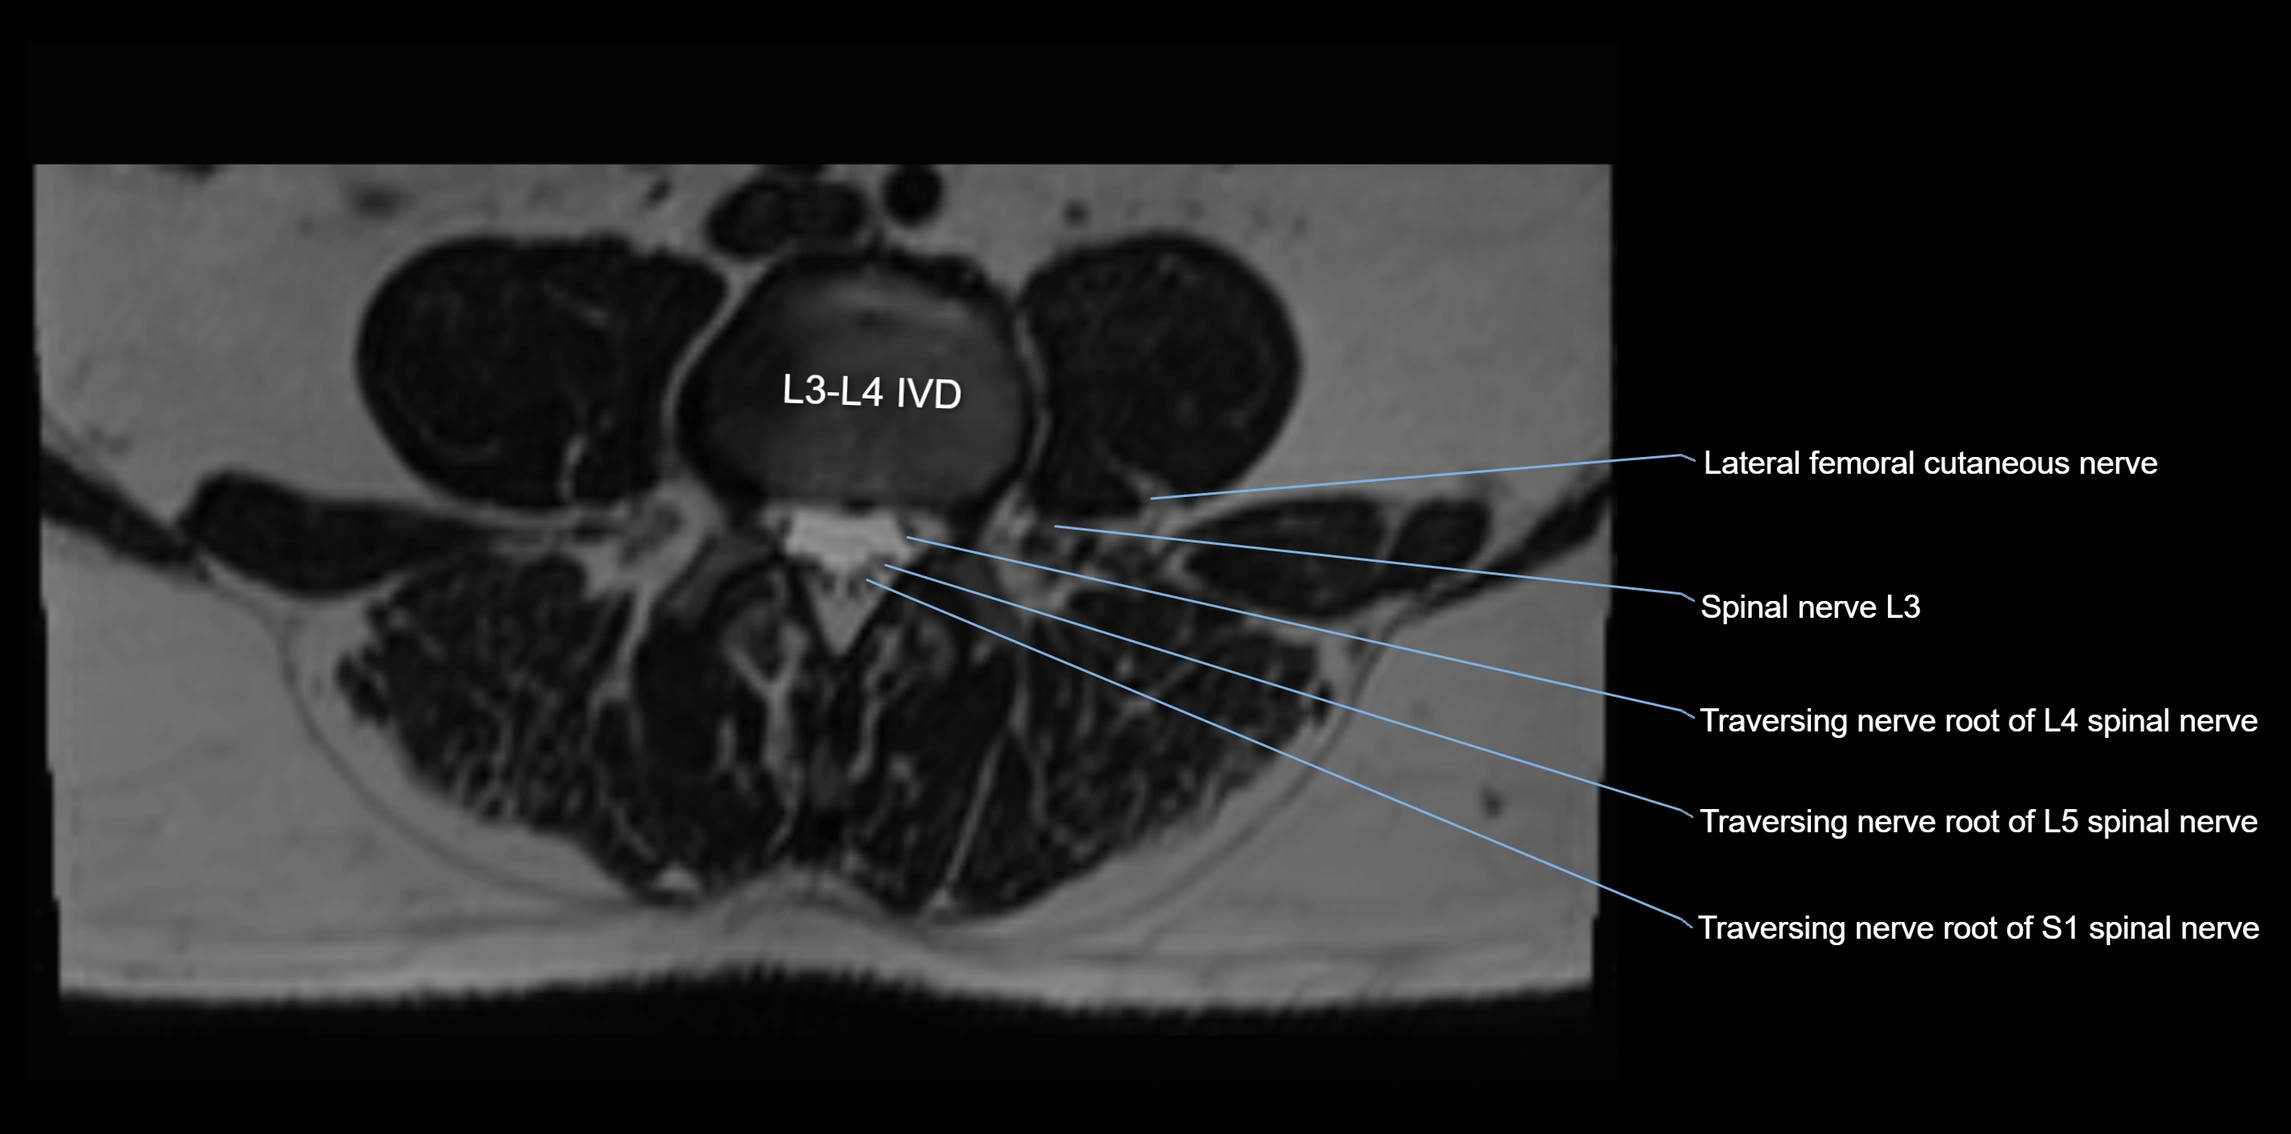

MRI Appearance

T1-weighted images:

• Nerve appears as a very thin low-to-intermediate signal intensity structure

• Surrounded by bright fat, aiding visualization

T2-weighted images:

• Nerve shows intermediate to mildly hyperintense signal compared to muscle

• Pathological involvement appears brighter

STIR (Short Tau Inversion Recovery):

• Normal nerve appears dark

• Inflamed or entrapped nerve appears bright hyperintense

T1 Fat-Sat Post-Contrast:

• Normal nerve enhances minimally

• Pathologic nerve (neuritis, entrapment, tumor infiltration) shows focal or diffuse enhancement

3D T2 SPACE / CISS:

• Nerve appears intermediate to mildly hyperintense compared to muscle

• Surrounded by bright fat or CSF, improving visualization

• Best sequence for mapping small pelvic nerves such as the anococcygeal